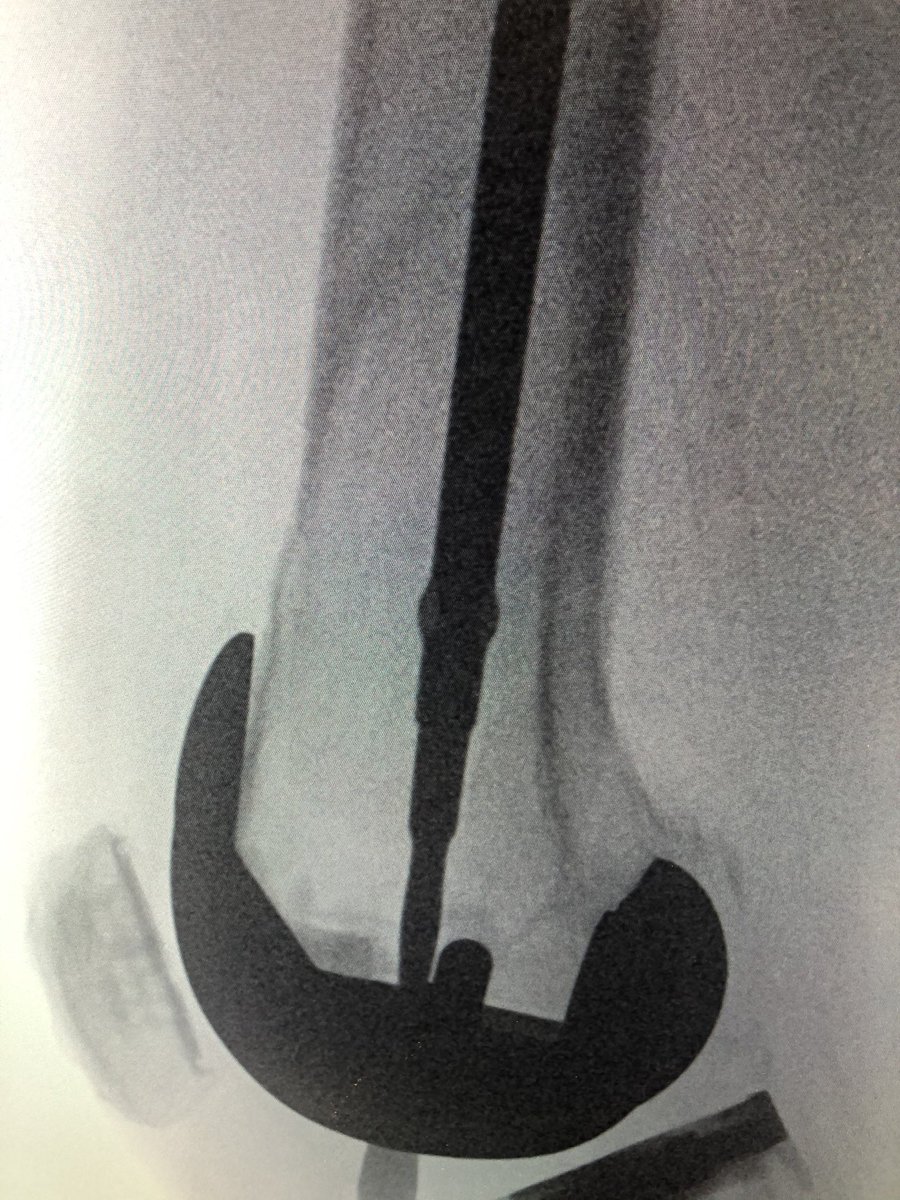

[3/5] Here is the Synthes colinear clamp reducing the fracture. Length was achieved by my resident pulling on the leg, and I got the correct rotation by putting my finger through the incision on the anterior femur, feeling the stepoff, and rotating the leg until it felt “right.”